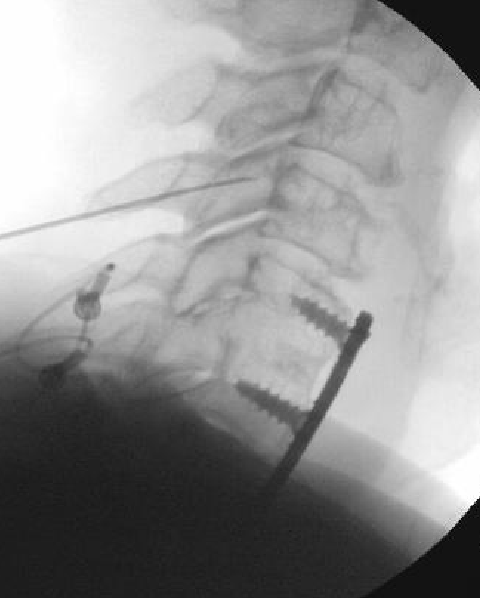

Nasty neuritis. This is 80 degrees 90 seconds.

These images look great. Sorry it happened? Steroid?

Lyrica Rx sent in, and we're starting it for chronic pain (and neuritis). She gets a shoulder scope in two weeks for a large RCT. I like antineuropathics (gabapentin 100mg HS or BID) perioperatively in general. I wish they were given 2 weeks before and after ALL orthopedic surgeries.

Dexamethasone given before RFA needles were removed.

Why are you doing RFA at a fused level?

i believe medicare will not cover RFA of a fused level.

i saw that too, but when you look at the AP images...